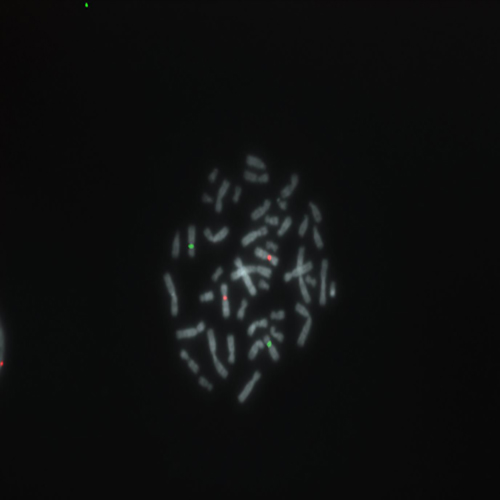

Hybridization of SE 7 / SE 8 probe to a metaphase spread showing normal pattern (2R2G).

Trisomy 8 is found as one of the genetic changes in CML, while loss of chromosome 7 is found in AML. The SE 7 (D7Z1)/SE 8 (D8Z1) FISH probes are optimized to detect repetitive sequences located in the pericentric heterochromatin of chromosome 7 and 8.